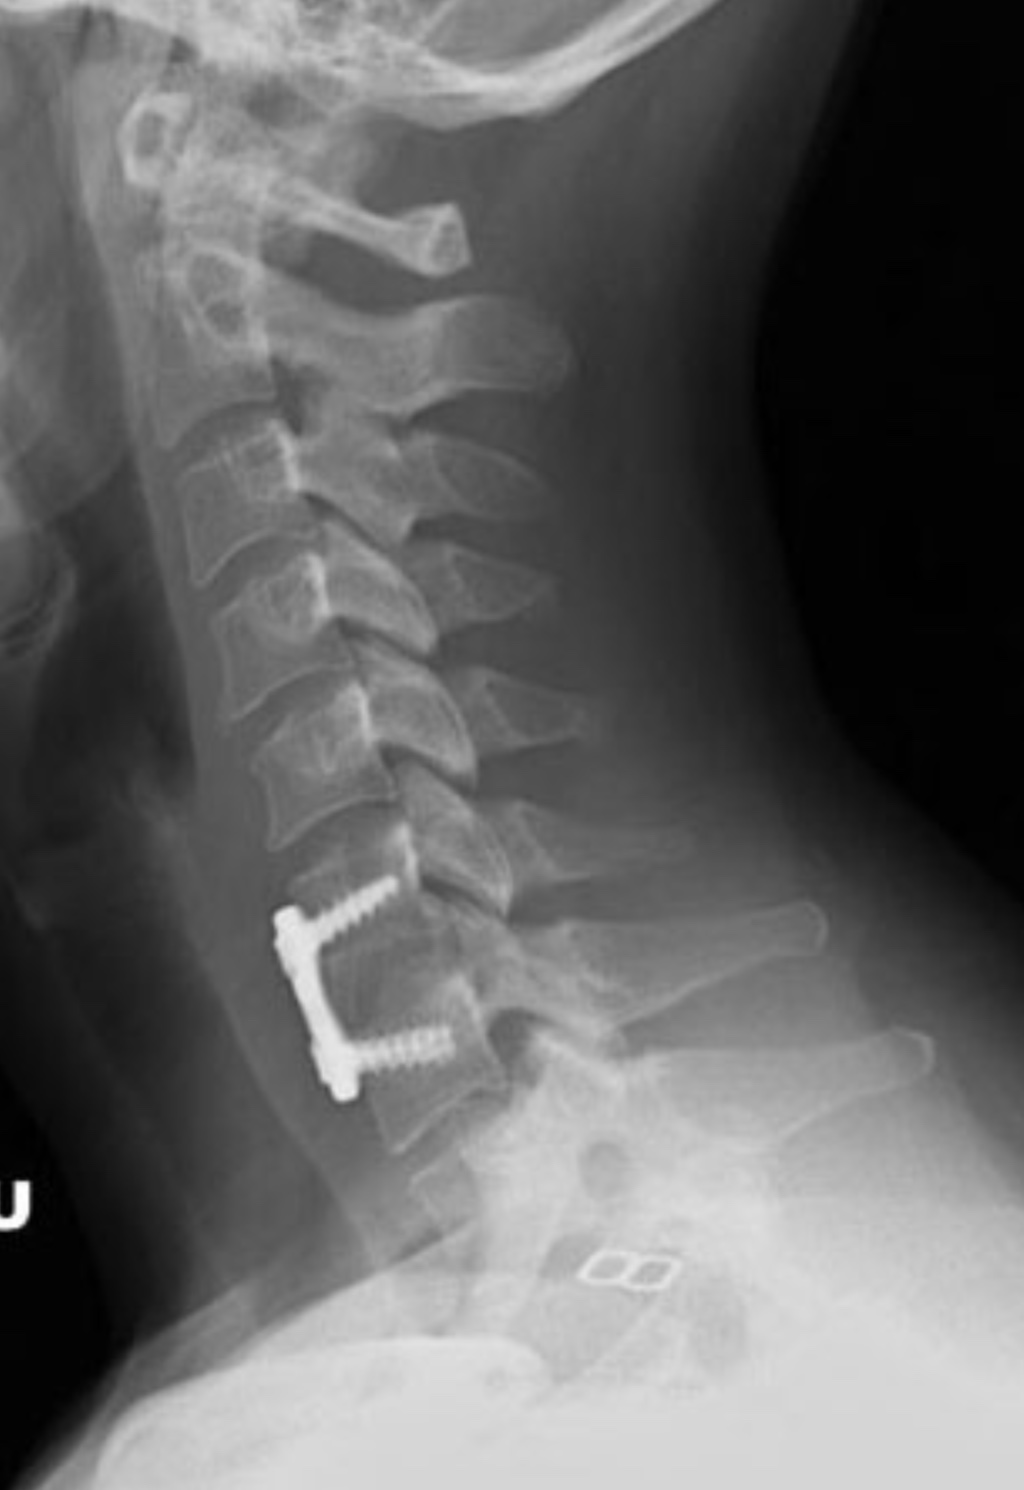

Surgery for cervical radiculopathy General center Cervical Radiculopathy Reddit I recently posted about my experiences with realizing that i have (99% probability) cervical radiculopathy, plus. I went to urgent care yesterday, which is where i was diagnosed with a trapezius strain and prescribed prednisone and flexeril, but i'm fairly. Cervical radiculopathy, commonly called a pinched nerve, occurs when a nerve in the neck is compressed or irritated where it. Cervical Radiculopathy Reddit.

Case study Cervical radiculopathy Injection NYSORA Cervical Radiculopathy Reddit I recently posted about my experiences with realizing that i have (99% probability) cervical radiculopathy, plus. If those nerves become damaged or inflamed, you have a condition called cervical radiculopathy — the umbrella term used to describe changes in nerve function in your cervical, or. On monday i had what started as my typical neck/upper back knot that progressed into. Cervical Radiculopathy Reddit.